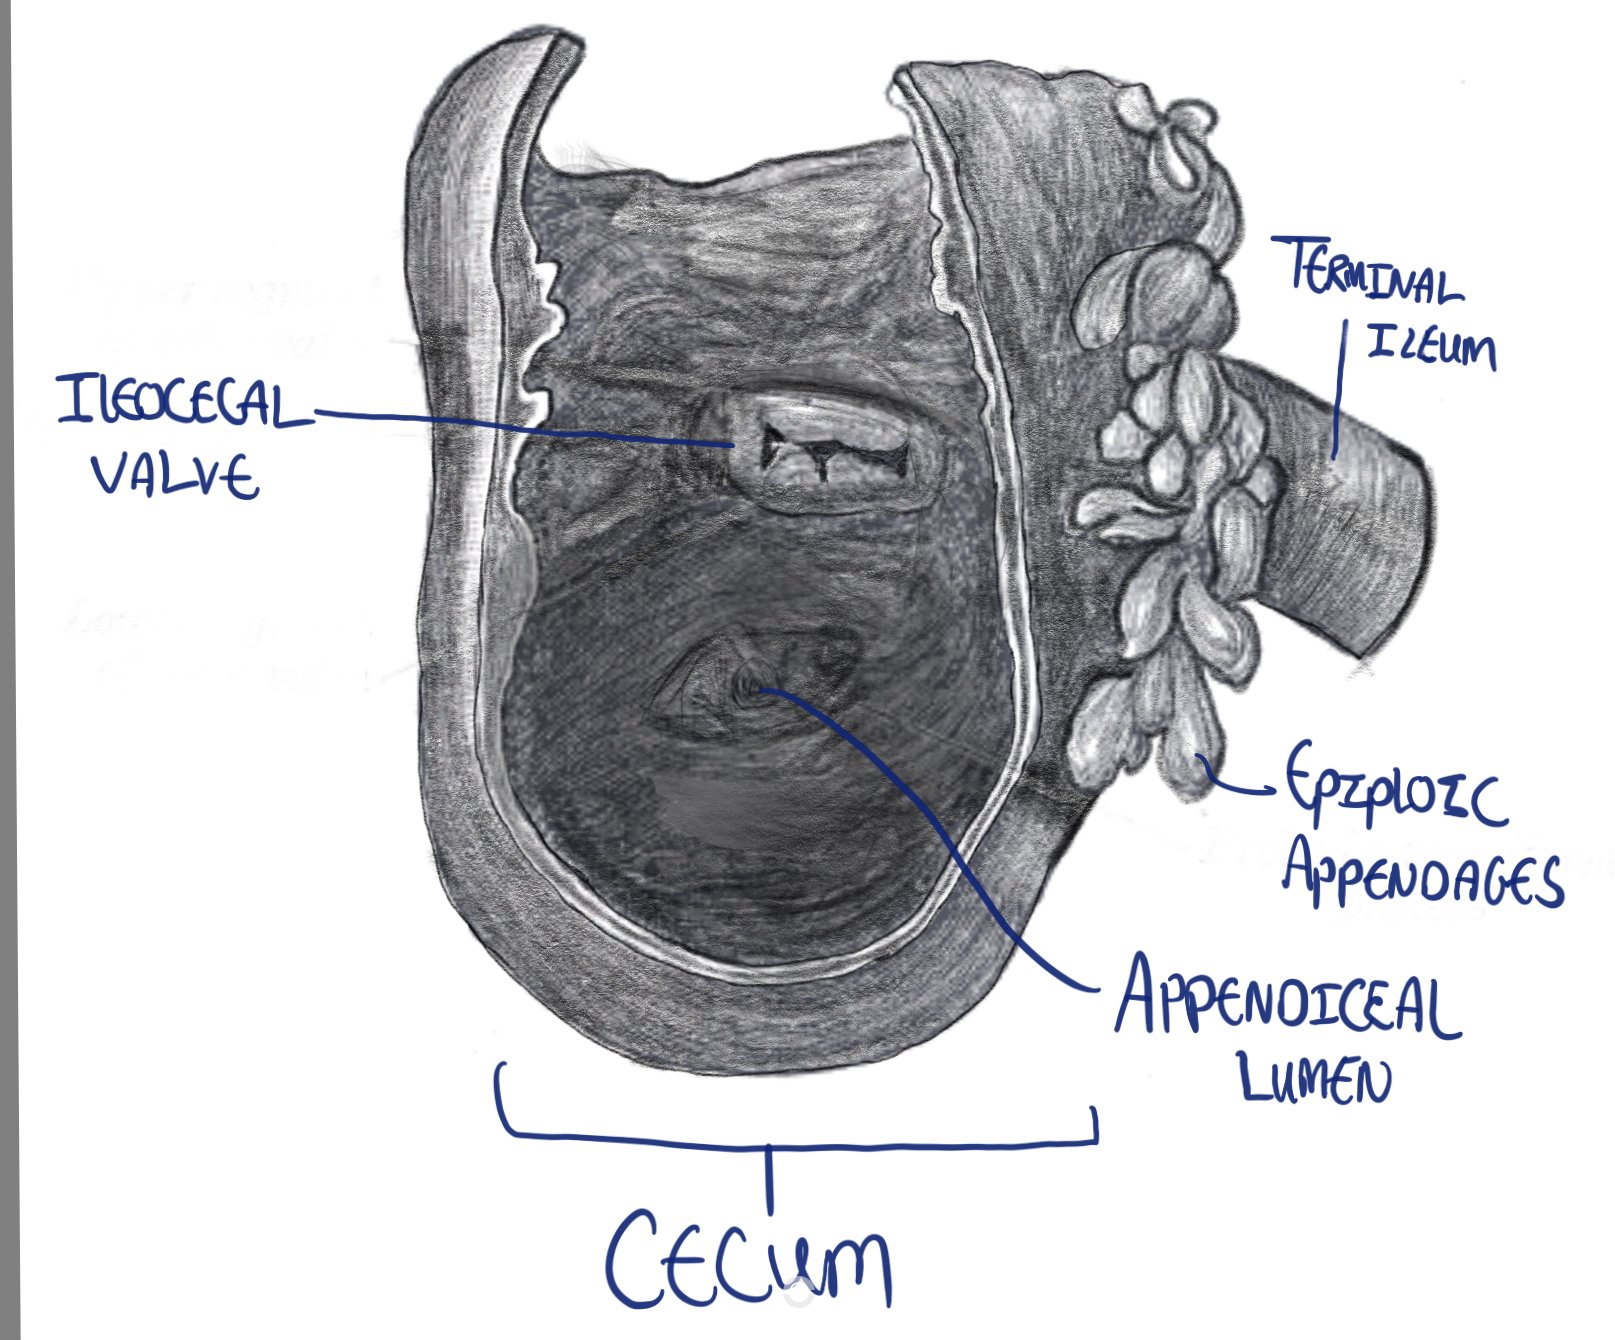

The vermiform appendix is a blind ended true diverticulum of the colon. It extends from the posteromedial aspect of the cecum, 2.5 cm inferior to the ileocecal valve, ending blindly in the right iliac fossa (RIF).

- It arises from the posteromedial aspect of the cecum.

- The cecum is a pouch forming the first part of the colon.

- The appendix arises posteriorly (behind) and from the medial aspect of it.

Drawing of the cecum, showing the ileocecal valve and appendiceal lumen.

- Appearances are very similar to the colon and cecum

- layers

- Mucosa: made of columnar epithelim <!!should be “epithelium”!!> with goblet and endocrine cells.

- submucosa: contains blood vessels, lymph nodes and connective tissue

- muscularis: inner circular muscular layer, lacks tinea <!!should be “taenia”!!>

- serosa: outer layer of visceral peritoneum.

- Distinct features (relates to the supposed immune function of the appendix)

- More presence of lymph follicles and parafollicular tissue in the connective tissue layer of the mucosa (lamina propria)

- M cells: microfold cells are foind <!!should be “found”!!> in the epithelium and can sample antigens and pathogens from the intestinal lumen.

- lacks tinea <!!should be “taeniae”!!>: outer muscle later <!!should be “layer”!!> is regular.

- The appendiceal lumen narrows with age and can become completely obliterated in the elderly, which is why appendicitis is less common in older adults.

- The narrowing and potential obliteration of the appendiceal lumen in older adults is directly related to the incidence of appendicitis in this age group. Specifically, appendicitis becomes less common in older adults. This reduced frequency of appendicitis in the elderly population can be attributed, at least in part, to these age-related changes in the appendix’s internal structure.

Lumen of the appendix